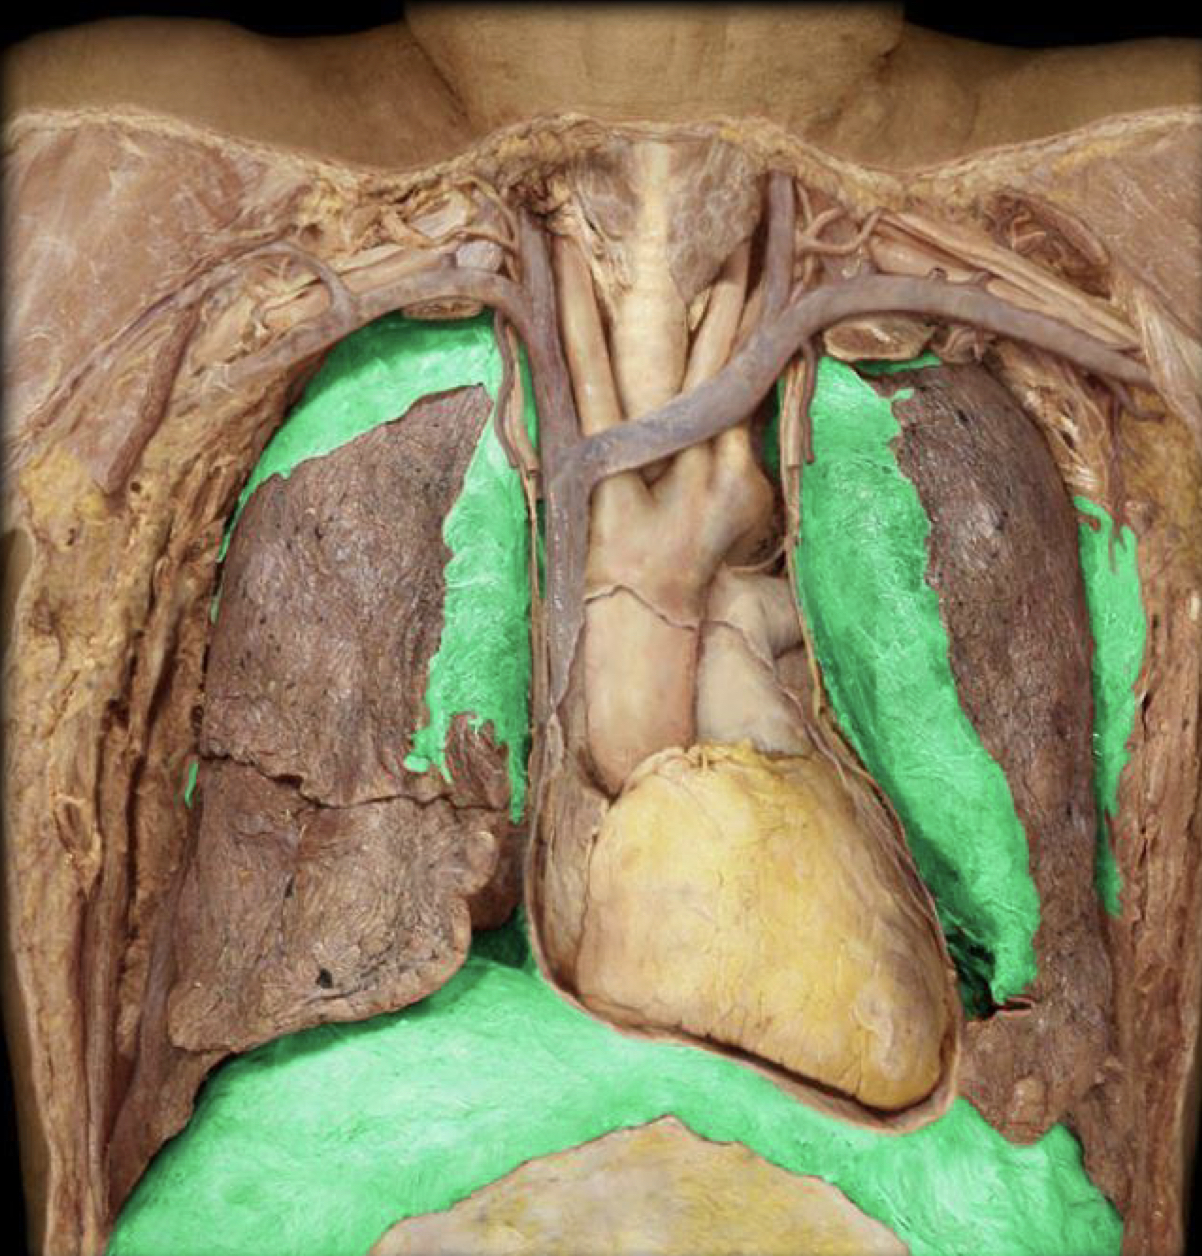

What structure is highlighted in green?

Visceral pleura

Parietal pleura